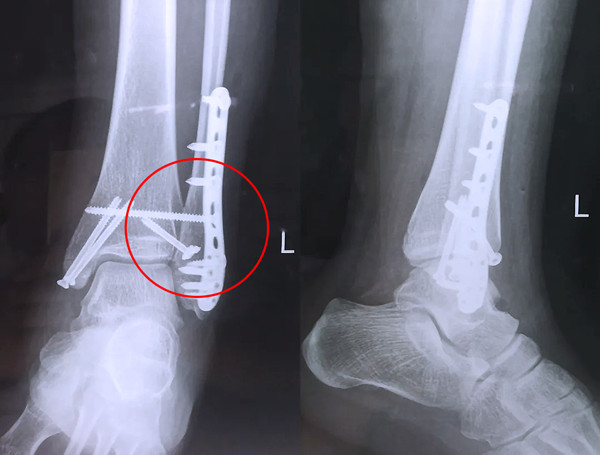

踝關節骨折在X影像上的表現有很多種。如內踝骨折和外踝骨折,我們可以在影像上看到骨折處的骨折線是不連續的。還有后踝的骨折,內踝、外踝、后踝聯合在一起發生的骨折,我們稱之為“三踝骨折”,這些都是在X影像上能夠顯示出來的。

【醫療科普】Pilon骨折

有一種特殊類型的踝關節骨折,可能在X影像平片上就不能顯示出來,它就是脛骨的關節面往里塌陷,我們又稱之為叫“Pilon骨折”。當它往里塌陷后,我們在X影像平片上可能看不出來它是否塌陷,但是我們在CT上可以360°看到踝關節的影像,這樣就可以看出患者是否存在踝關節塌陷的骨折。同樣道理,我們在做Pilon骨折手術的時候,普通二維的X影像并不能判斷我們手術復位情況的好壞,這個時候如果醫生手上有能夠照三維影像的工具,那么對于醫生的準確手術是非常有好處的。